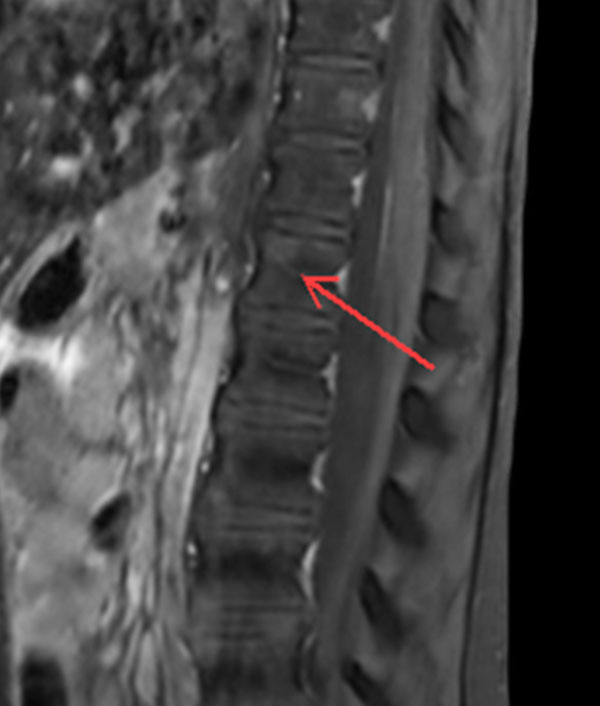

Premium Fat-free Pediatric Spine imaging

Phoenix Children Hospital, USA